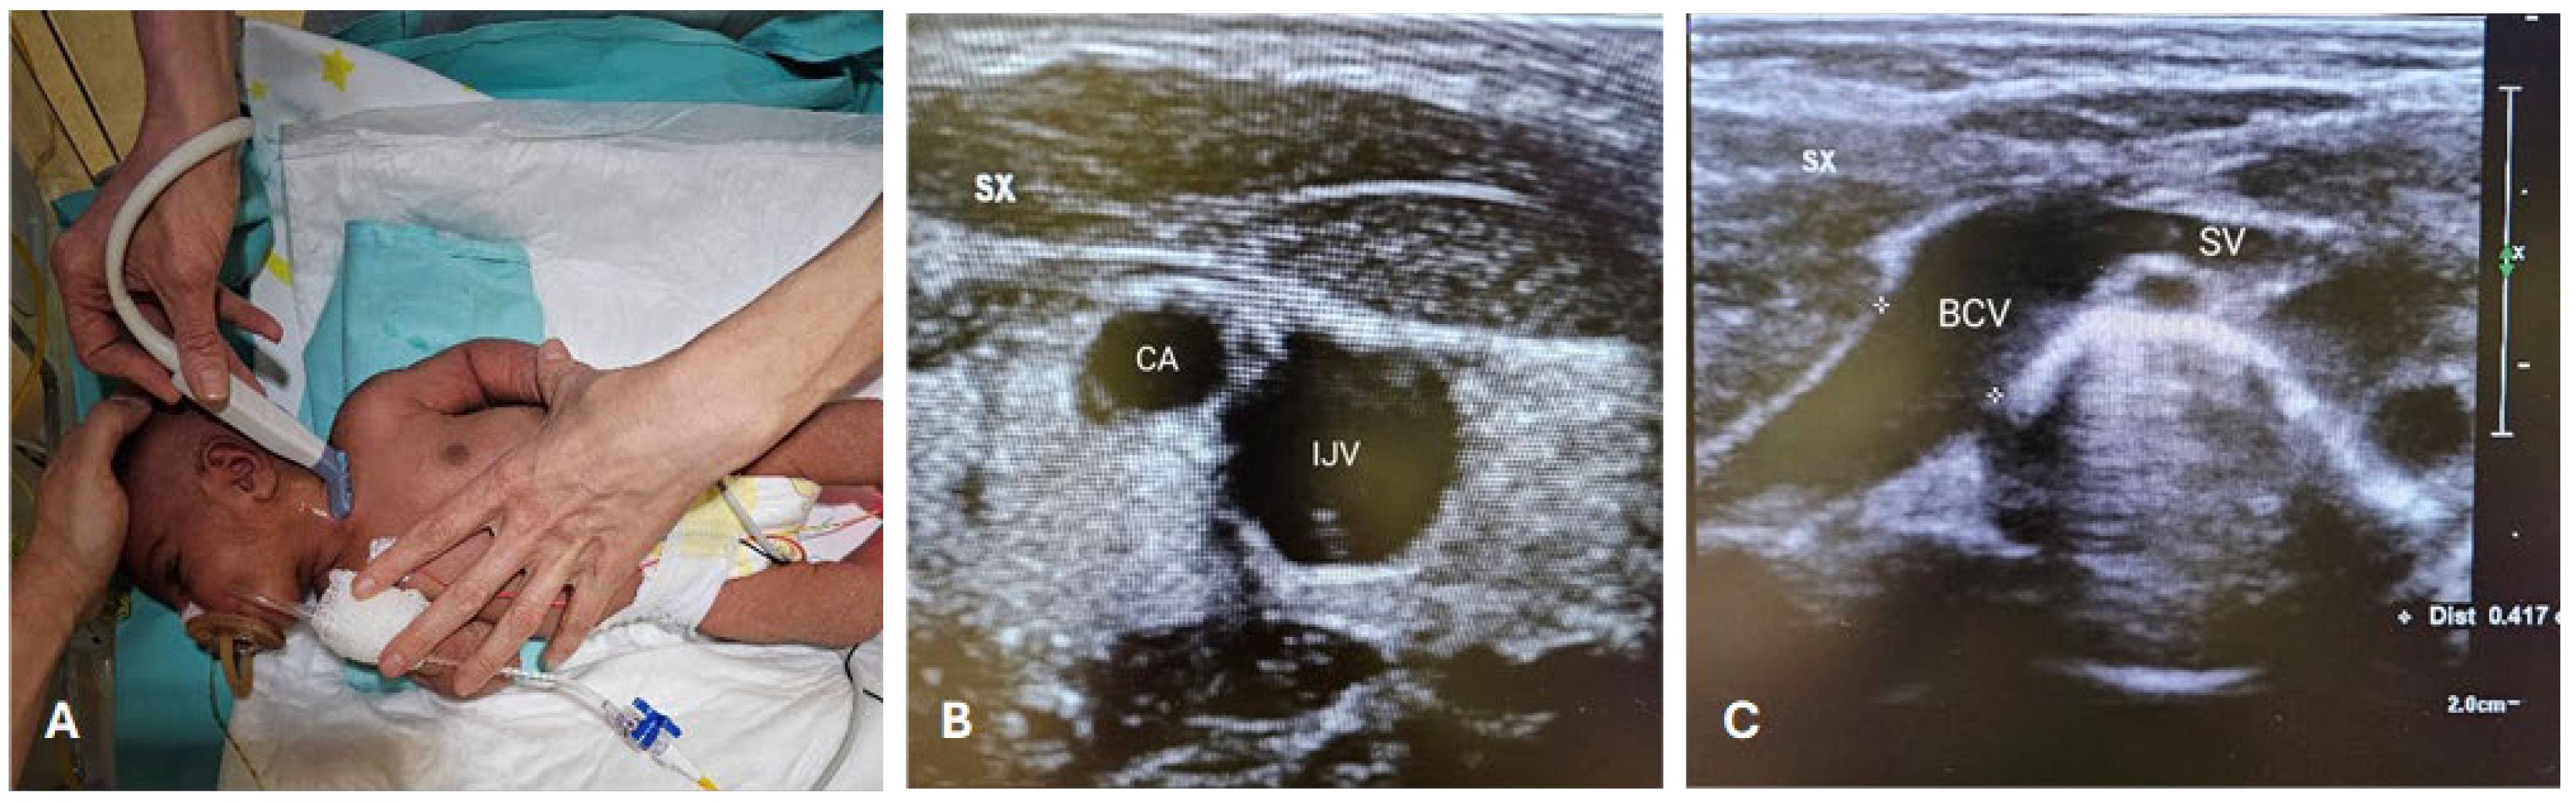

The CICC placement procedures (Figure 1 and Figure 2) were performed under sedo-analgesia with ketamine (1–2 mg/kg) and midazolam (50–150 μg/kg) for infants ≥33 weeks gestational age (GA) or fentanyl (1–2 μg/kg) for infants <33 weeks GA. In addition, a pacifier with 24% sucrose per os (0.2–0.5 mL or 1–2 mL for preterm and term infants, respectively) was offered in the preparatory phase, a quiet environment was provided (noise was reduced), and appropriate position and containment were achieved. Proper local anaesthesia at the CVC insertion site in case of tunnelling, with subcutaneous infiltration of lidocaine 1% (buffered lidocaine solution with sodium bicarbonate; maximum dose 0.5 mL/kg), has also been used.

During the procedures, the neonate was positioned supine, with the neck slightly extended and the head turned towards the opposite side of the chosen BCV (Figure 1A). The primary operator was positioned on the same side as the venipuncture site (Figure 1A). Intraprocedural ultrasound was performed with a Philips’ L15-7io linear array intraoperative hockey stick US probe transducer connected to a Philips EPIQ 7C ultrasound unit. Power-injectable, polyurethane non-valved catheters of 22 G—2 Fr single lumen or 3 Fr double lumen were placed (60 mm length). The optimal catheter size was selected following the indications by the WOCOVA-GAVECELT-WINFOCUS consensus and the INS standards, which recommend a catheter to vein ratio of 1:3 [25,26,27]. We measured the vein’s diameter in order to match it with the catheter size and reduce the risk of venous thrombosis (Figure 1B,C).

Figure 1. RACEVA protocol. Pre-operative US scan with the so-called RACEVA (Rapid Central Vein Assessment) protocol. (A) Systematic US examination of the veins in the supra-clavicular/sub-clavicular area; (B) US localization of CA and IJV; (C) US localization of BCV and SV. Abbreviations. BCV: brachio-cephalic vein; CA: carotid artery; IJV: internal jugular vein; SV: subclavian vein; SX: left; US: ultrasound.